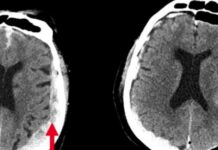

Επιστήμονες κατέγραψαν για πρώτη φορά τι συμβαίνει στον εγκέφαλο όταν πεθαίνουμε

Για πρώτη φορά, επιστήμονες κατέγραψαν τι συμβαίνει στον εγκέφαλο τη στιγμή που ο άνθρωπος πεθαίνει. Οι ερευνητές που έκαναν τη συγκεκριμένη ανακάλυψη διαπίστωσαν ότι η...